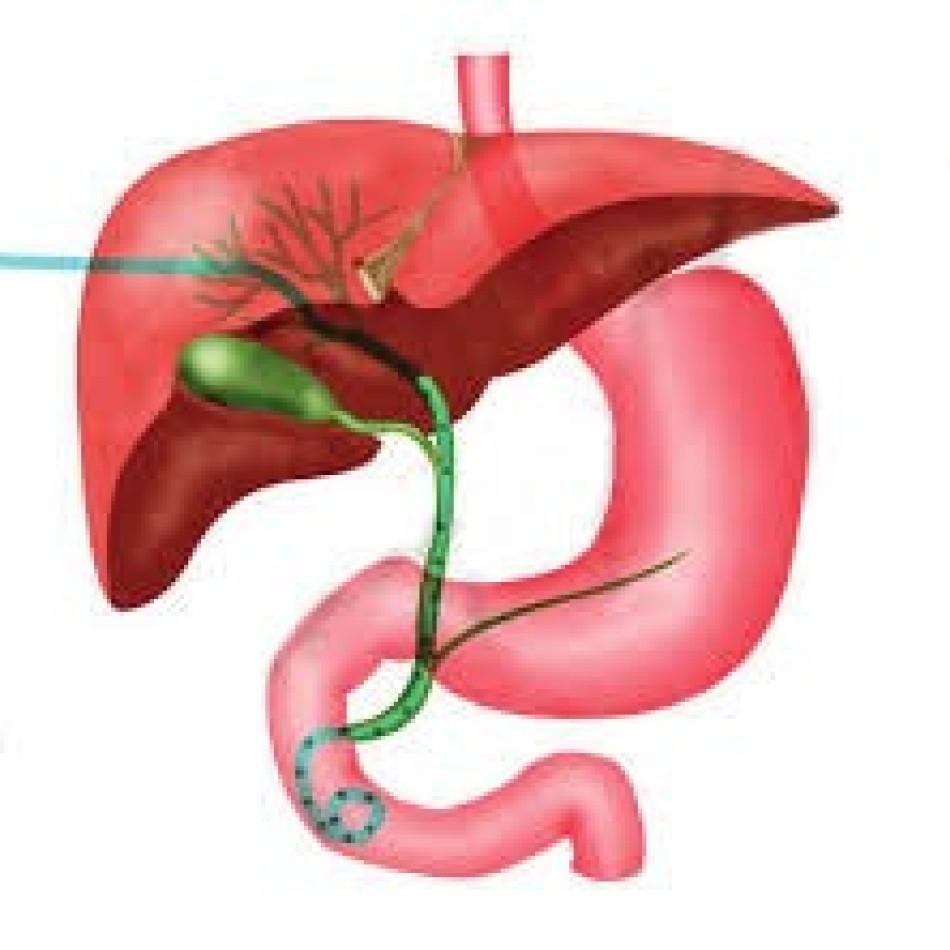

Bij een galwegontsteking (cholangitis) zijn de galwegen in of buiten de lever ontstoken. In de lever zitten veel kleine galkanaaltjes. Deze komen samen in de grotere galwegen. Via de grotere galwegen wordt de galvloeistof afgevoerd naar de galblaas en vervolgens naar de dunne darm. De galblaas.. Auszug. Die extra hepatischen Gallen wege in Form des Gallengangs und der Gallenblase garantieren den großen täglichen Bedarf an fettemulgierender Galle. Jede Unwegsamkeit darin provoziert ein Stenosemuster mit entsprechendem Gallenrückstau, der akut zum tödlichen Leberversagen und chronisch zu einem fibrodestruktiven Reaktionsmuster und.

ERCP (Endoscopische Retrograde Cholangio en Pancreaticografie) Informatiefolders

Naar huis met een percutane galwegdrain (PTC) St. Antonius Ziekenhuis

HPBchirurgie lever, galblaas/galwegen en alvleesklier Informatiefolders

Als cellen aan de binnenkant van de galweg ongecontroleerd gaan delen, kan er een kwaadaardige tumor ontstaan. Zo'n tumor heet galwegkanker of cholangiocarcinoom. Kanker van de galwegen is zeldzaam. De galwegen liggen in de bovenbuik en zorgen voor het vervoer van gal. Gal is een vloeistof die zorgt voor het verteren van de vetten in onze.. Merke. Obwohl für eine definitive Diagnose von Gallenwegstrikturen oftmals eine histologische Aufarbeitung mittels Biopsie oder Operation notwendig ist, können radiologisch relevante Eigenschaften einer Stenose wie Asymmetrie, unscharfe Begrenzung oder Art der KM-Aufnahme auf eine maligne Erkrankung hinweisen.